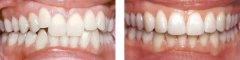

牙齿拥挤怎么治疗?

牙齿拥挤在生活中很常见,不仅会影响人的容貌,还会影响人的交际,所以牙列...【详细】

不同情况的牙齿拥挤怎么矫正?

牙齿拥挤让人的形象受损,让人感觉很尴尬,给生活带来很多不便,在现代每个...【详细】